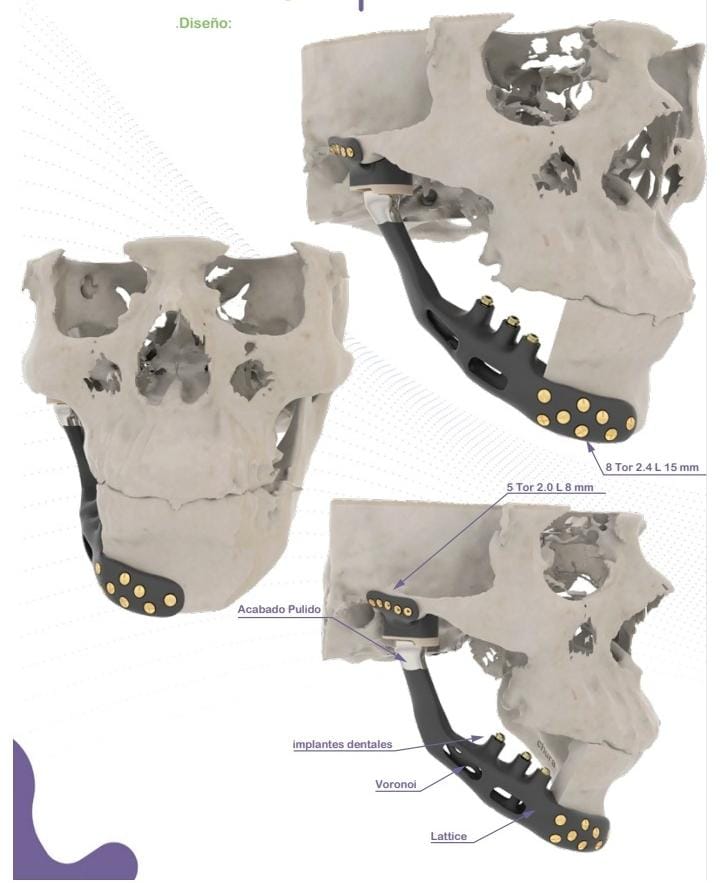

Esta tecnología no solo se aplica en cirugía buco máxilo cráneo facial, sino también en cirugía ortopédica.

Diseño a medida

Cada implante se fabrica adaptado a la anatomía específica del paciente, mejorando la precisión y el resultado clínico.

Captura y Modelado 3D

La reconstrucción anatómica se realiza a partir de imágenes obtenidas mediante técnicas de diagnóstico como Tomografía Axial Computada (TAC) o Resonancia Magnética (MRI). Estas imágenes son procesadas con software especializado para modelar en tres dimensiones cualquier región anatómica, incluso con patologías complejas.

Inclusión de Implantes

En el modelado digital 3D se pueden incluir implantes ortopédicos como placas, tornillos, mallas, prótesis y otros dispositivos, diseñados en tamaño real y en relación directa con la anatomía del paciente. Esto permite simular distintos escenarios quirúrgicos antes de la cirugía.

Ver másCirugía Maxilofacial

Implantes adaptados a la anatomía facial del paciente, planificación quirúrgica digital y reducción de tiempos en sala de operaciones.